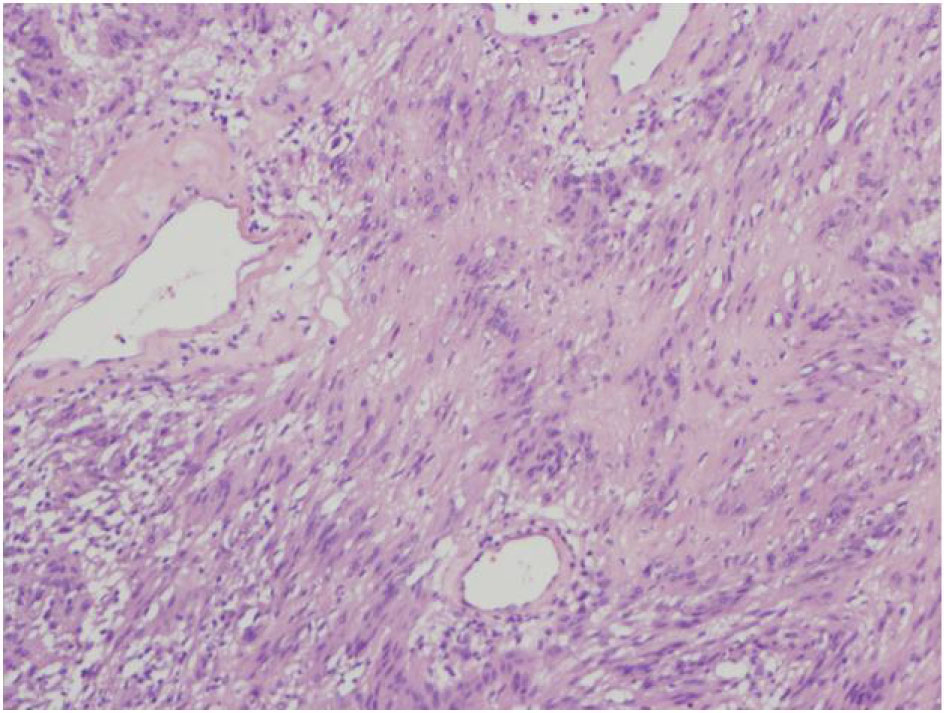

The final pathology demonstrated a 23 × 14.5 × 13.5 cm, 2590 grams, multiloculated, cystic mass (Fig. 4, 5) consistent with ancient schwannoma characterized by a proliferation of spindle cells (Fig. 6), Antoni type A and type B (Fig. 7) and strong positivity for S-100 protein (Fig. 8). The post-operative period was uneventful and patient was discharged home day 5 after surgery. At 11-month follow-up, the patient is free from recurrence.

![]() Click for large image | Figure 7. 4X HE varocay. |

Microscopically, the tumor contains varying proportions of Antoni A and B histologies [10]. Antoni-A is composed of spindle cells with elongated nuclei, forming interlacing bundles with focal nuclear palisading and lacks mitotic figures [11]. However, Antoni-B is less cellular and lacks distinct architectural features [10, 11]. Strong positively for S-100 is a requisite for diagnosis [11]. Since fine needle aspiration or biopsy cannot provide a definitive histological diagnosis [8], surgical resection is typically recommended to confirm diagnosis, obtain local control and mitigate symptoms when present.